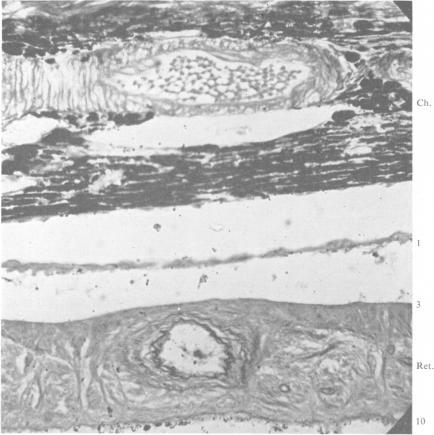

Degenerations of the dog retina. III. Retinopathy secondary to glaucoma.

Br J Ophthalmol. 1953 Nov;37(11):670-9. doi: 10.1136/bjo.37.11.670.